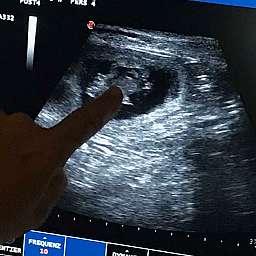

12.6.2018, 30.Tag: Um 11.00Uhr startete unser großer Moment: Adeles Wunder wurde von unserer Tierärztin geschallt.

Wir sind überglücklich Euch mitteilen zu dürfen, daß Adele tragend ist. Beim Ultraschall sahen wir völlig überwältigt 4 - 5 kleine Fruchthüllen mit pochenden Herzen darin.